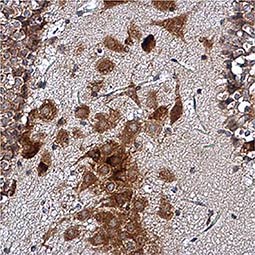

GeneTex is honored to host Dr. Carl Laflamme, a senior postdoctoral research fellow in the laboratory of the distinguished Dr. Peter McPherson at McGill University’s Montreal Neurological Institute. Dr. Laflamme’s work has focused on understanding the mechanisms underlying amyotrophic lateral sclerosis (ALS) with particular emphasis on C9orf72, a gene whose disruption represents the most common genetic cause of ALS/frontotemporal dementia (FTD). In addition, he is currently spearheading the ALS Reproducible Antibody Platform (ALS-RAP) that is dedicated to leveraging CRISPR/Cas9 knockout technology to identify reliable commercial antibodies for ALS/FTD research.

In his talk, Dr. Laflamme will discuss his published work describing the systematic assessment of antibodies against the C9ORF72 protein as part of ALS-RAP. He will then present intriguing data regarding C9ORF72 biology in macrophages, and will introduce his very exciting and potentially revolutionary efforts to expand the ALS-RAP methodology for antibodies against additional ALS disease proteins as well as those of other neurodegenerative disorders. Dr. Laflamme will explain how this approach will be further broadened and amplified to address the commercial antibody reliability crisis in biomedical research.